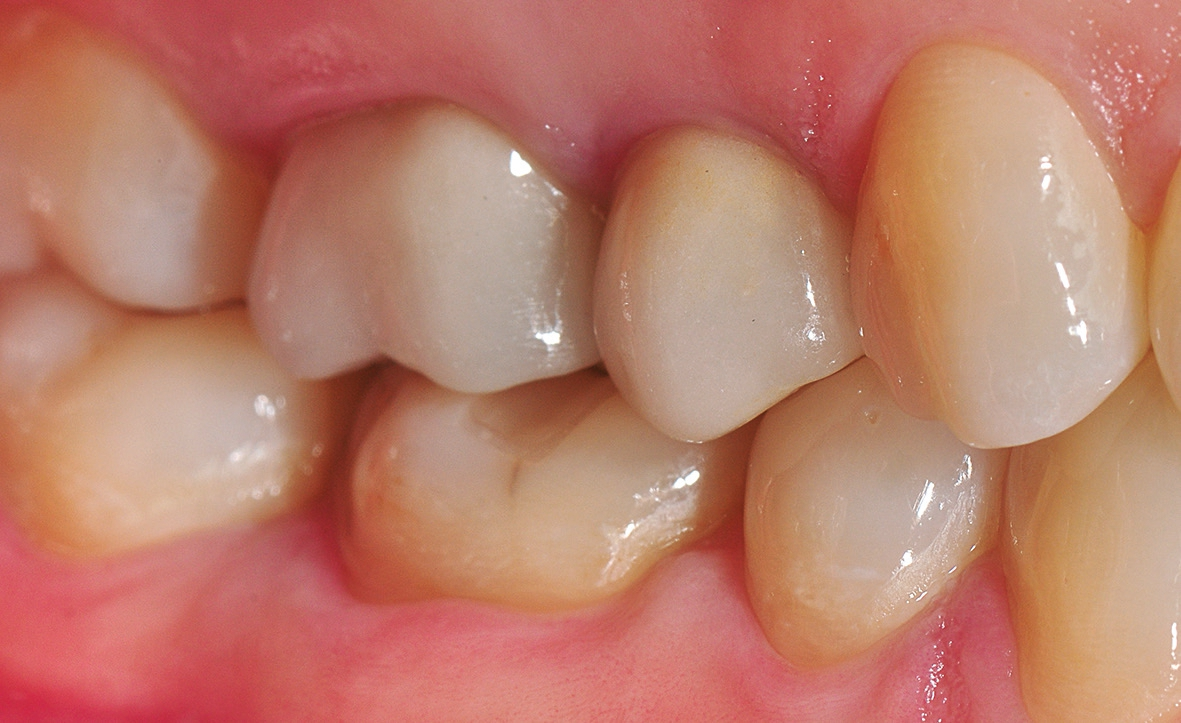

Nach einer komplikationsfreien Einheilzeit von vier Monaten konnte mit der Herstellung des definitiven Zahnersatzes begonnen werden. Hier entschied man sich konsequent für monolithische Kronen aus Lithiumdisilikat, um das Chippingrisiko so gering wie möglich zu halten [12]. Im Zuge der Implantatversorgung wurde nun auch – wie geplant – die metallkeramische Krone an 16 geschlitzt, entfernt und der Stumpf nachpräpariert. Implantatkopf und Zahnstumpf wurden daraufhin zusammen mit A-Silikon analog abgeformt. Für die geschlossene Abformung wurde die Abformkappe (impression.transfer) auf dem Implantatkopf positioniert. Ein deutliches Einrasten signalisierte den lagestabilen Sitz. Für die Modellherstellung rastete das Implantatanalog (lab. replica) ebenso in die integrierte Abformkappe ein. Nach der Herstellung des Meistermodells konnten die beiden Kronen im digitalen Workflow CAD/ CAM-gestützt gefertigt werden. Nach Ausarbeitung, Bemalung und Glasur waren die beiden Kronen für die definitive Zementierung bereit. Die klinische Einprobe der Restaurationen verlief erfolgreich, sodass die Kronen nacheinander mit selbstadhäsivem Befestigungskomposit eingegliedert werden konnten.